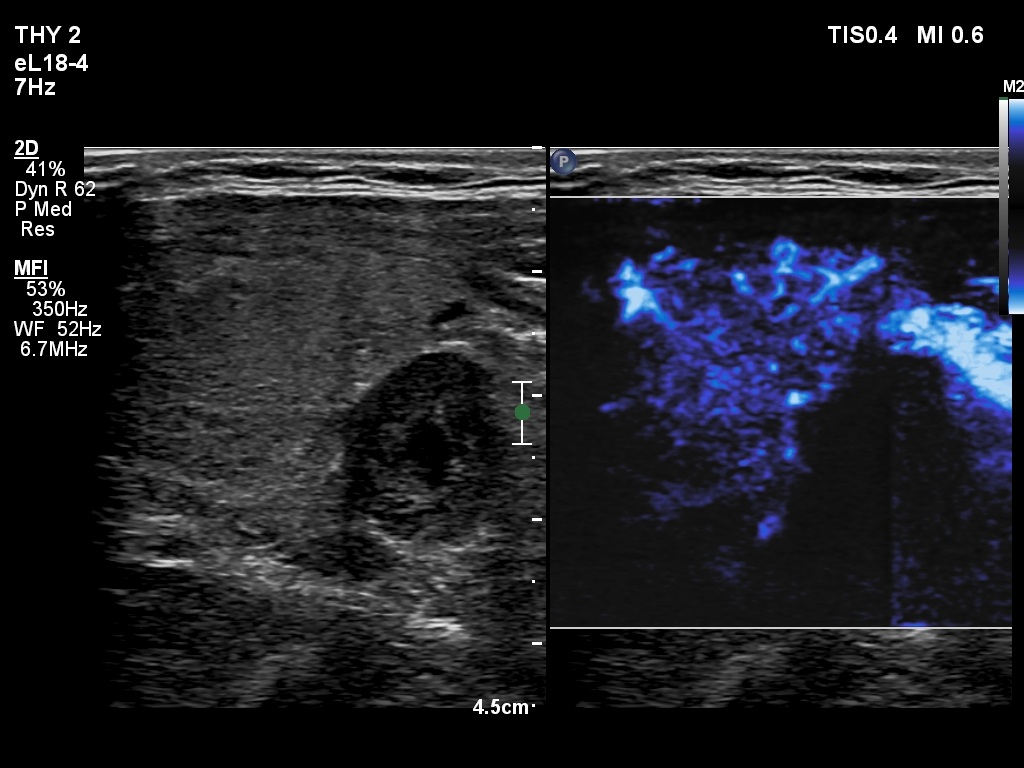

Right lobe, longitudinal scan

Lower part of the left thyroid bed, transverse scan, microflow imaging. The mass in question presents no vascularization.